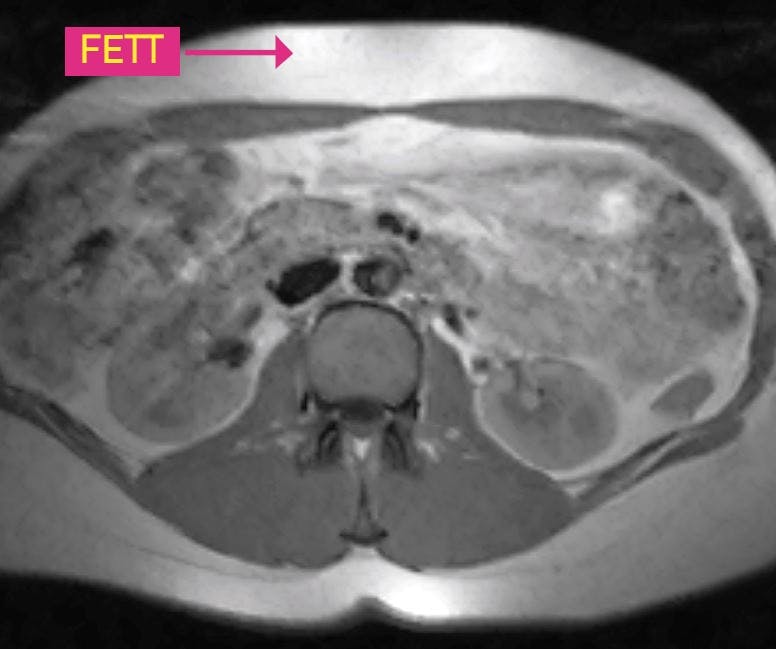

FÖR MYCKET BUKFETT PRECIS UNDER HUDEN Magen i tvärsnitt. Personen här har en del bukfett (det vita ) precis under huden, men inte mycket fett mellan inälvorna.

För mycket bukfett mellan inälvorna

FÖR MYCKET BUKFETT MELLAN INÄLVORNA Magen i tvärsnitt. Personen här har både mycket bukfett (det vita) precis under huden och mellan inälvorna.